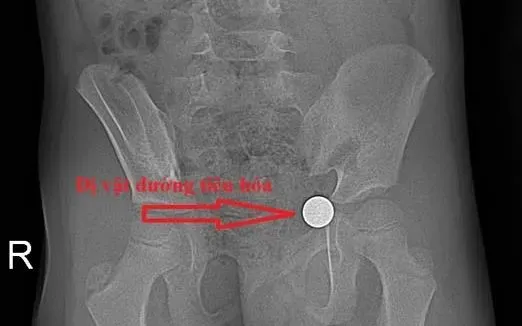

Qua kiểm tra và chụp X-quang, các bác sĩ phát hiện dị vật dạng viên bi đã di chuyển xuống đường tiêu hóa dưới. Sau khi đánh giá tình trạng, bệnh nhi được chỉ định điều trị nội khoa và theo dõi chặt chẽ.